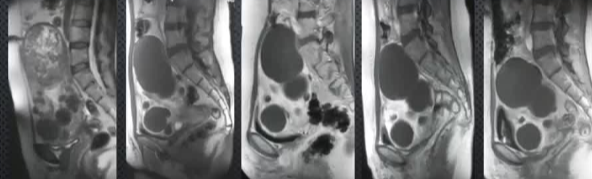

![]() 分别是基线→3月→1年→2年→3年 【Pelage JP 2004】 子宫肌瘤有治疗有需求,子宫动脉栓塞术(UAE)具有应用价值。本研究通过3年MR随访,旨在评估UAE治疗子宫肌瘤后的长期磁共振(MR)成像结局,探讨UAE治疗后肌瘤梗死程度与长期预后的关联,为临床疗效评估提供影像学依据。 方法概述采用增强MR成像,动态监测肌瘤体积、灌注及症状变化,通过组间比较(t检验、卡方检验)分析梗死程度对结局的影响。研究对象为20例患者,在UAE术前、术后3个月及每年随访(最长3年)进行对比增强盆腔MR成像,分析肌瘤梗死程度、体积变化、症状改善及新发肌瘤情况。其中17例患者在基线、治疗后3个月和3年进行了对比增强MR成像。 核心结果